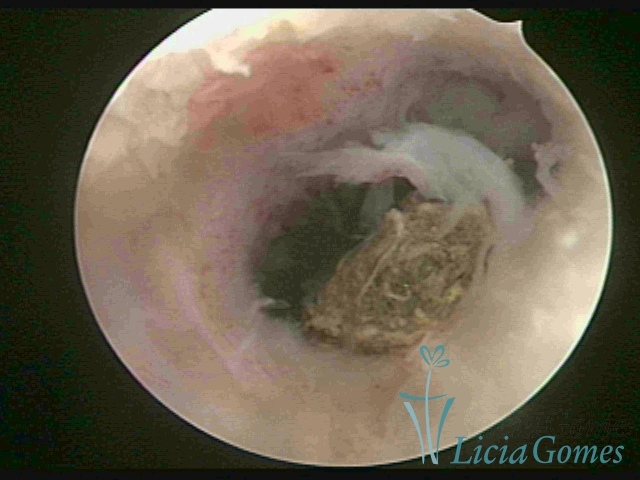

Uterine cavity with a fragmented IUD debris, inserted 46 years ago.

×